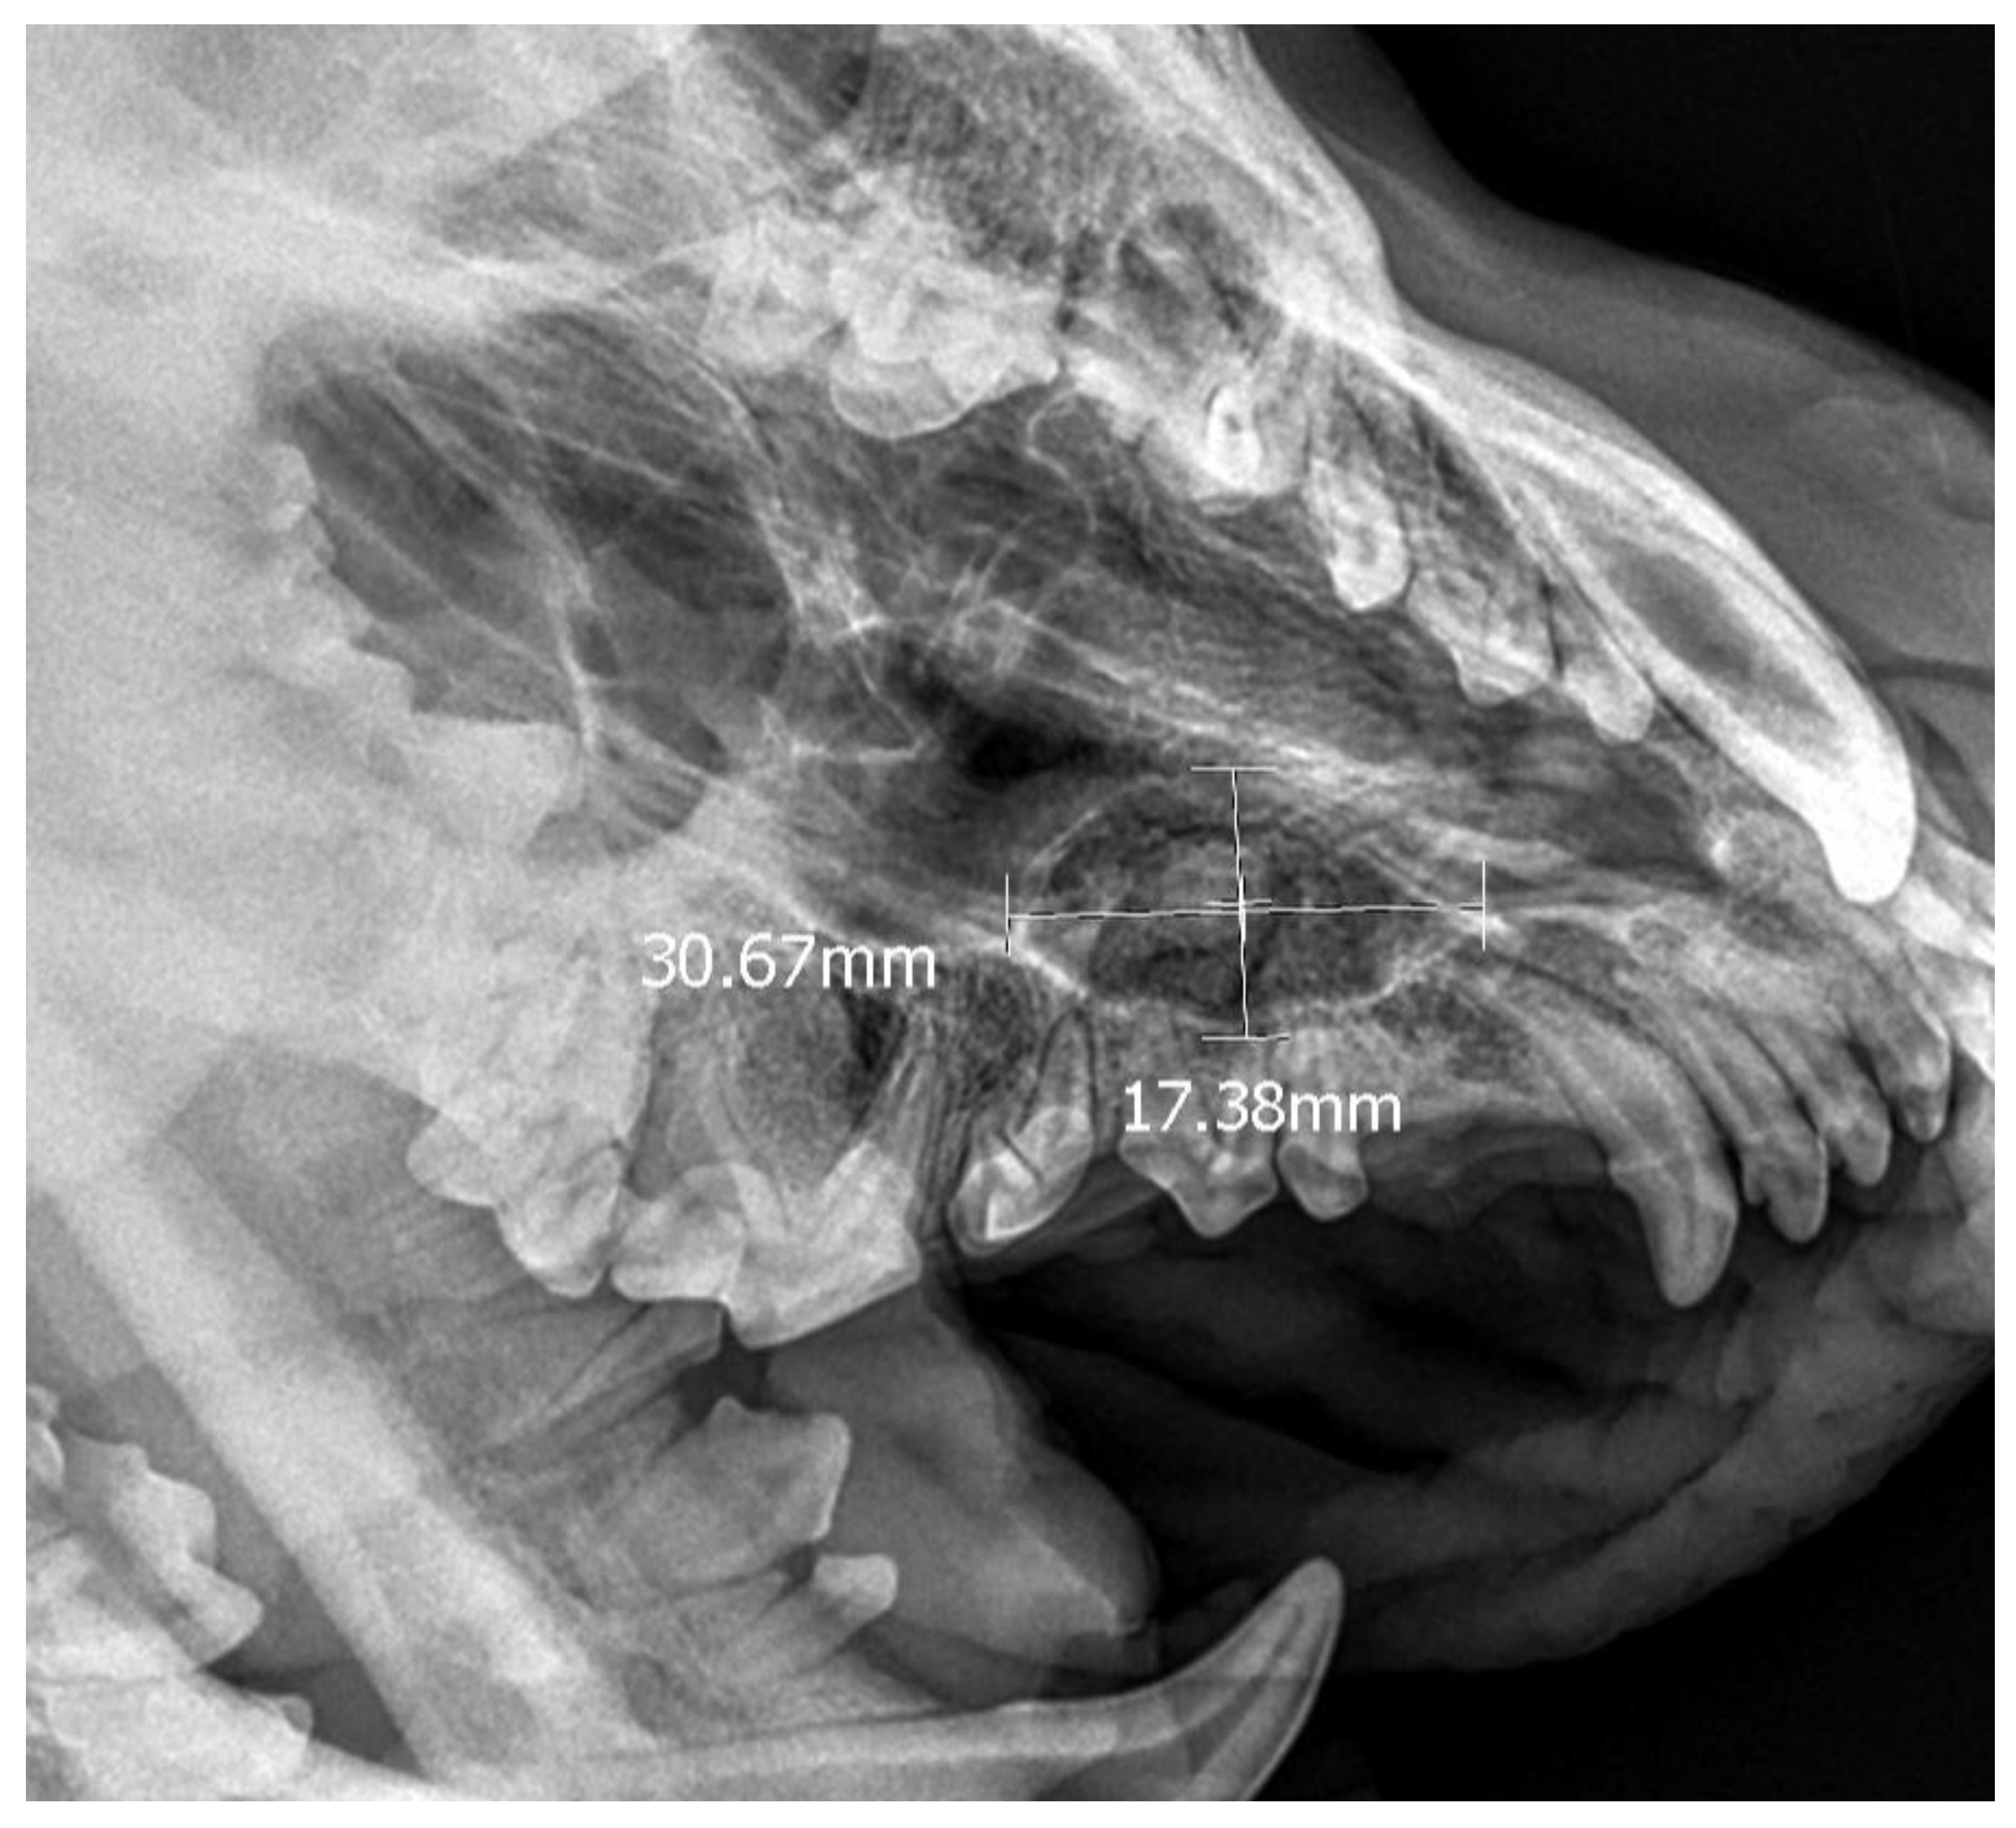

A 7-month-old male Rottweiler was referred for consultation because of severe swelling on the left side of the jaw, with a suspected jaw tumor. Clinical examination revealed no abnormalities in the aforementioned lymph glands and no soreness on palpation. Intraoral examination on the left side revealed severe asymmetry, with enlargement of the facial soft and hard tissues, an absence of permanent teeth, and buccal displacement of deciduous teeth. On the left side, rhinoscopic examination revealed normal anterior nostrils and a left nasal aperture with a lack of patency from the level of the nasal bony inlet to the posterior nostrils. A roentgenogram in the dorsal–ventral projection showed the presence of four ectopic teeth in the maxilla, with the formation of a dentigerous cyst (Figure 2). Using the CLP technique, the ectopic teeth were removed and the cyst walls were lanced. The bone loss caused by the cyst was 7.3 cm × 4.6 cm, and the jawbone left behind was too thin to provide a scaffold for the surrounding tissues and to ensure nasal cavity patency. From a 5 cm pellet of hydroxyapatite polymer material with curdlan previously soaked in saline (according to the manufacturer’s instructions), longitudinal flaps of 5 cm long, 1 cm wide, and 0.1–0.2 cm thick were cut and placed in the bony defect to strengthen the bony scaffolding of the jaw and nasal septum (Figure 3). The gingival flap was sutured with a single suture using 4-0 monofilament material. The first radiological follow-up was performed after 4 weeks, but due to the size of the defect and the size of the pellets of material used, the hydroxyapatite obscured the structures in the nasal cavity, preventing accurate assessment. A rhinoscopic examination revealed patency of the left nasal cavity. It was decided to conduct a radiological follow-up 6 months after the procedure, but the owner, for personal reasons, did not attend the follow-up appointment. After 12 months, another roentgenogram was performed, where a properly healed jawbone with closure of the cyst cavity could be observed. The nasal septum was formed properly, and the resulting bony scaffolding resulted in patency of the left nasal aperture, along with normal airflow on the left side (Figure 4).

Figure 5. X-ray in oblique head projection. The image shows an ectopic tooth along with an alveolar cyst (the dimensions of the cyst are marked).